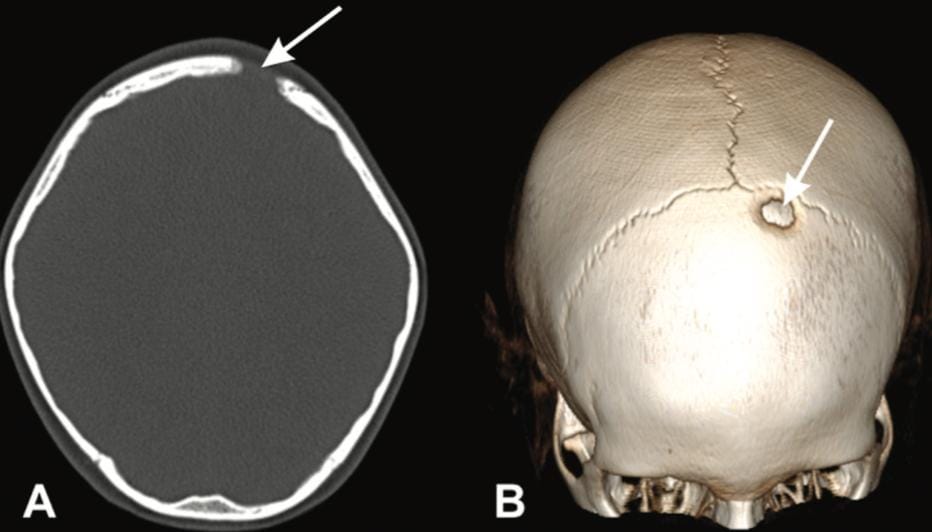

Histiocitose de Células de Langerhans no Sistema Nervoso Central, Ossos Cranianos e Espinhais: achados de imagem

A Histiocitose de Células de Langerhans (LCH) é uma doença rara, de caráter neoplásico, marcada pela proliferação monoclonal de células dendríticas patológicas, frequentemente associada à…